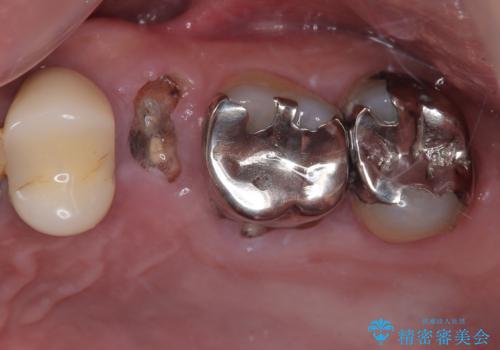

最新の症例

Latest cases